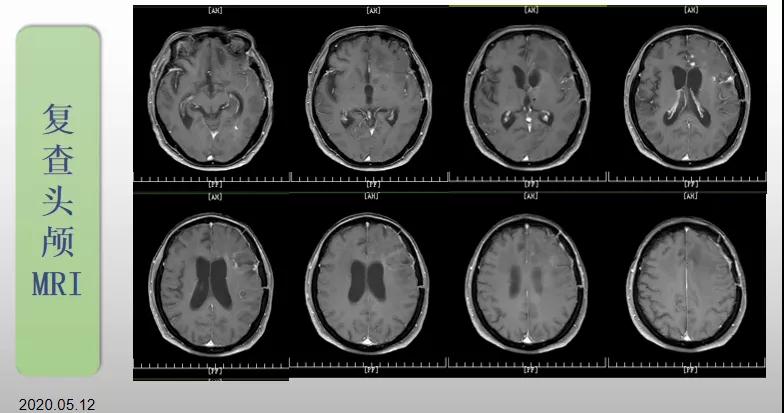

綜合治療 電場治療助70歲患者回歸正常生活

70歲的郝女士去年曾在外院查出“左額島葉”膠質(zhì)母細(xì)胞瘤(WHO Ⅳ級),并做了左側(cè)額島葉占位性病變切除術(shù)。術(shù)后進行了同步放化療。由于治療條件有限,郝女士慕名來到我院就診。賀世明主任率領(lǐng)醫(yī)護團隊立即為郝女士進行了全面的檢查,決定為其進行綜合治療 電場治療。經(jīng)過三個多月的綜合治療,患者復(fù)查頭顱MRI病變較前明顯縮小。出院時,郝女士神志清醒,睡眠飲食正常,說話很流利?!拔沂翘芍M來的,現(xiàn)在不用人攙扶,自己就可以走出病房了。”郝女士拉著醫(yī)護人員的手說。